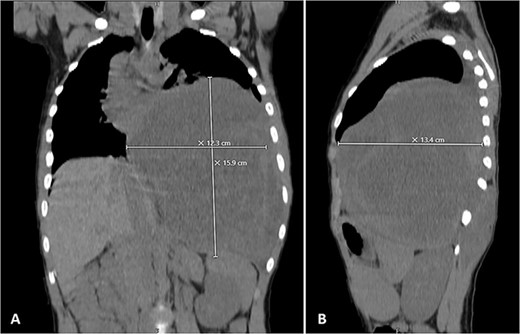

Physical examination unveiled a painless, solid mass characterized by hardness, emerging from the left lower chest and measuring 13 × 15 × 2 cm. This mass exhibited adherence to its surroundings, with no apparent pathological vasculature (Fig. 1). After this examination, a chest CT was conducted, revealing a huge, well-defined, and heterogeneous mass lesion occupying the left lower hemi-thorax. This imposing mass resulted in a noticeable reduction in left lung volume and a significant rightward mediastinal shift, measuring ~13.4 × 15.9 × 12.3 cm (Figs 2 and 3).

Selected coronal (A) and sagittal (B) cuts showing the size and the extension of the previously mentioned mass.